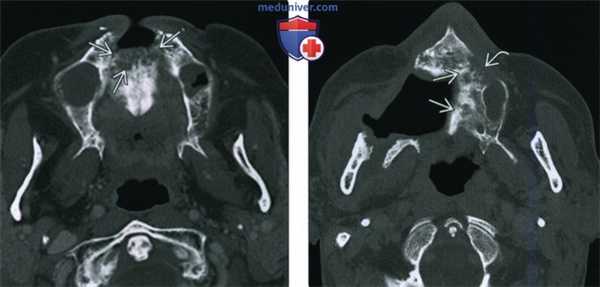

(Слева) При аксиальной КТ в коаном окне у пациента, получавшего лучевую терапию по поводу ПКР носовой перегородки, определяются литические изменения в передних отделах верхней челюсти, визуализируется фрагмент разрушенной кости.

(Справа) При аксиальной КТ в костном окне у другого пациента определяются изменения, обусловленные резекционным вмешательством на небе справа, видны также очаги литического и склеротического характера в верхней челюсти слева, которая также была подвергнута облучению. Верхняя челюсть относительно устойчива к лучевому воздействию и мало подвержена ОРН. Лучевые признаки ОРН верхней челюсти идентичны таковым для нижней челюсти, других костей лицевого скелета и основания черепа.

(Слева) При аксиальной КТ в костном окне у пациента, получавшего лучевую терапию по поводу плоскоклеточного рака носовой перегородки, визуализируется очаг литического характера в передних отделах верхней челюсти, представляющий собой треугольный участок деструкции костной ткани.

(Справа) При аксиальной КТ в костном окне у другого пациента определяются признаки выполненной резекции неба справа, а также изменения смешанного (склеротического и литического) характера в верхней челюсти слева, которая подвергалась облучению. Верхняя челюсть является относительно устойчивой к ионизирующему излучению, в ней редко возникает остеорадионекроз. Лучевые признаки идентичны таковым при поражении других костей лицевого скелета и основания черепа.